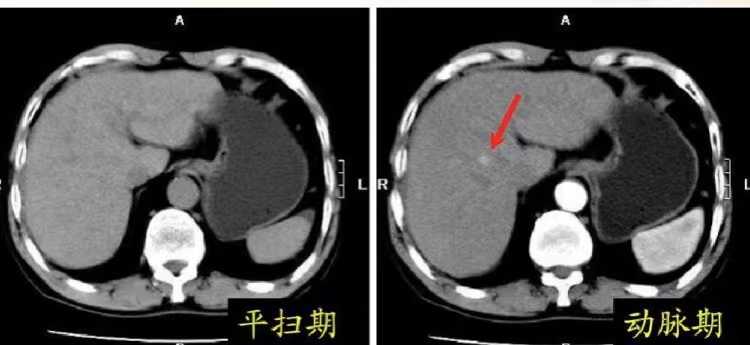

如果把平扫CT看作 “透视眼” ,那么增强CT就是 “放大镜” :对比剂在CT图像上呈白色,其它大部分人体组织多呈不同程度灰色,通过静脉注射对比剂之后,对比剂会通过血液循环,进入到病灶的血管并流出分布到病灶中。我们在注射对比剂的同时进行CT扫描,就可以通过观察病变中对比剂的分布,观察病变中血液循环的改变。同时通过对比剂分布的不同,增加病灶与周围正常组织的 “色差” ,清晰地显示病灶性质和范围,提供更丰富的病灶信息。

3、已经确认了是恶性肿瘤要进行分期分级,更准确的判断病变范围。以肝癌为例,最新的指南就推荐使用增强CT检查进行无创、精准的诊断及分期。